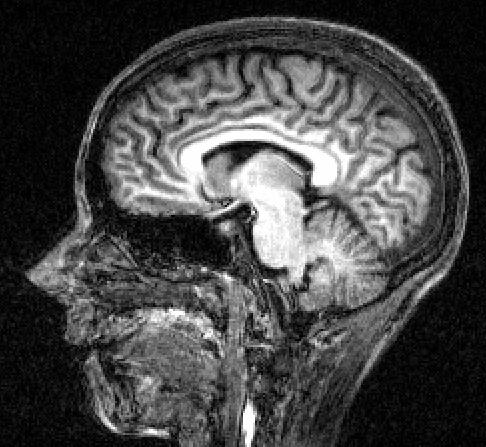

A picture of my brain. Even I can see there is no tumour there! Not as much grey matter as I would have hoped either. Hey ho

P.S. You have a beautiful hippocampus (hope I’m not being too fresh).